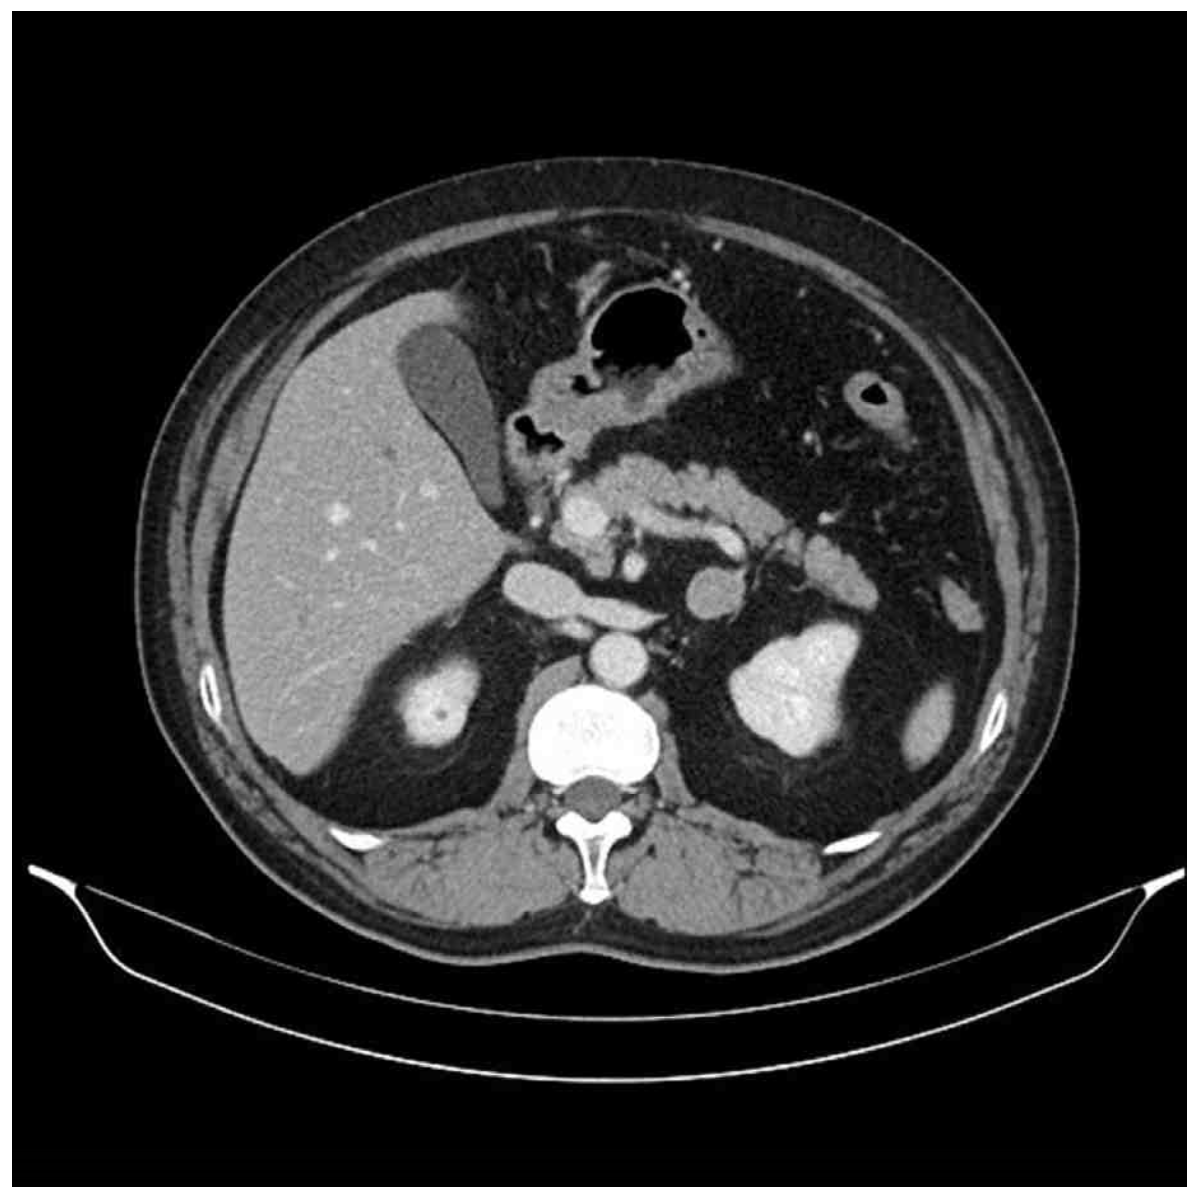

32세 남자가 6개월 전부터 두통이 있어서 병원에 왔다. 6개월 전부터 고혈압으로 진단받고 칼슘통로차단제, 이뇨제, 안지오텐신수용체억제제를 복용하고 있다. 키 176cm, 몸무게 76kg, 혈압 160/110 mmHg, 맥박 98회/분, 호흡 20회/분, 체온 36.5°C이다. 검사 결과는 다음과 같다. 복부 컴퓨터단층촬영 사진이다. 치료는?

Img | CT: Lt. adrenal mass |

PA 환자에서 40세 미만이고 unilateral adrenal mass가 확인되므로 부신절제를 실시한다.

• CT상 Lt. adrenal mass가 확인된다. 40세 미만에서 unilateral mass가 확인되므로 laparoscopic adrenalectomy를 실시한다.